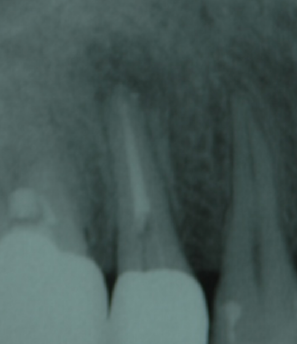

当院では「マイクロスコープ」という歯科用顕微鏡を使用しております。マイクロスコープでは、肉眼の何十倍もの視野が得られます。以下の画像をご覧ください。 同じ部位を「肉眼」と「マイクロスコープ」で見た場合の視野の違いをご確認いただけます。

マイクロスコープによる数十倍の拡大視野で、細部にわたり正確に感染部位を特定し、しっかり治療を行うことができます。また、当院のマイクロスコープは動画撮影機能が付いており、治療の様子を記録し、患者さん自身にもご確認いただけるようにしています。